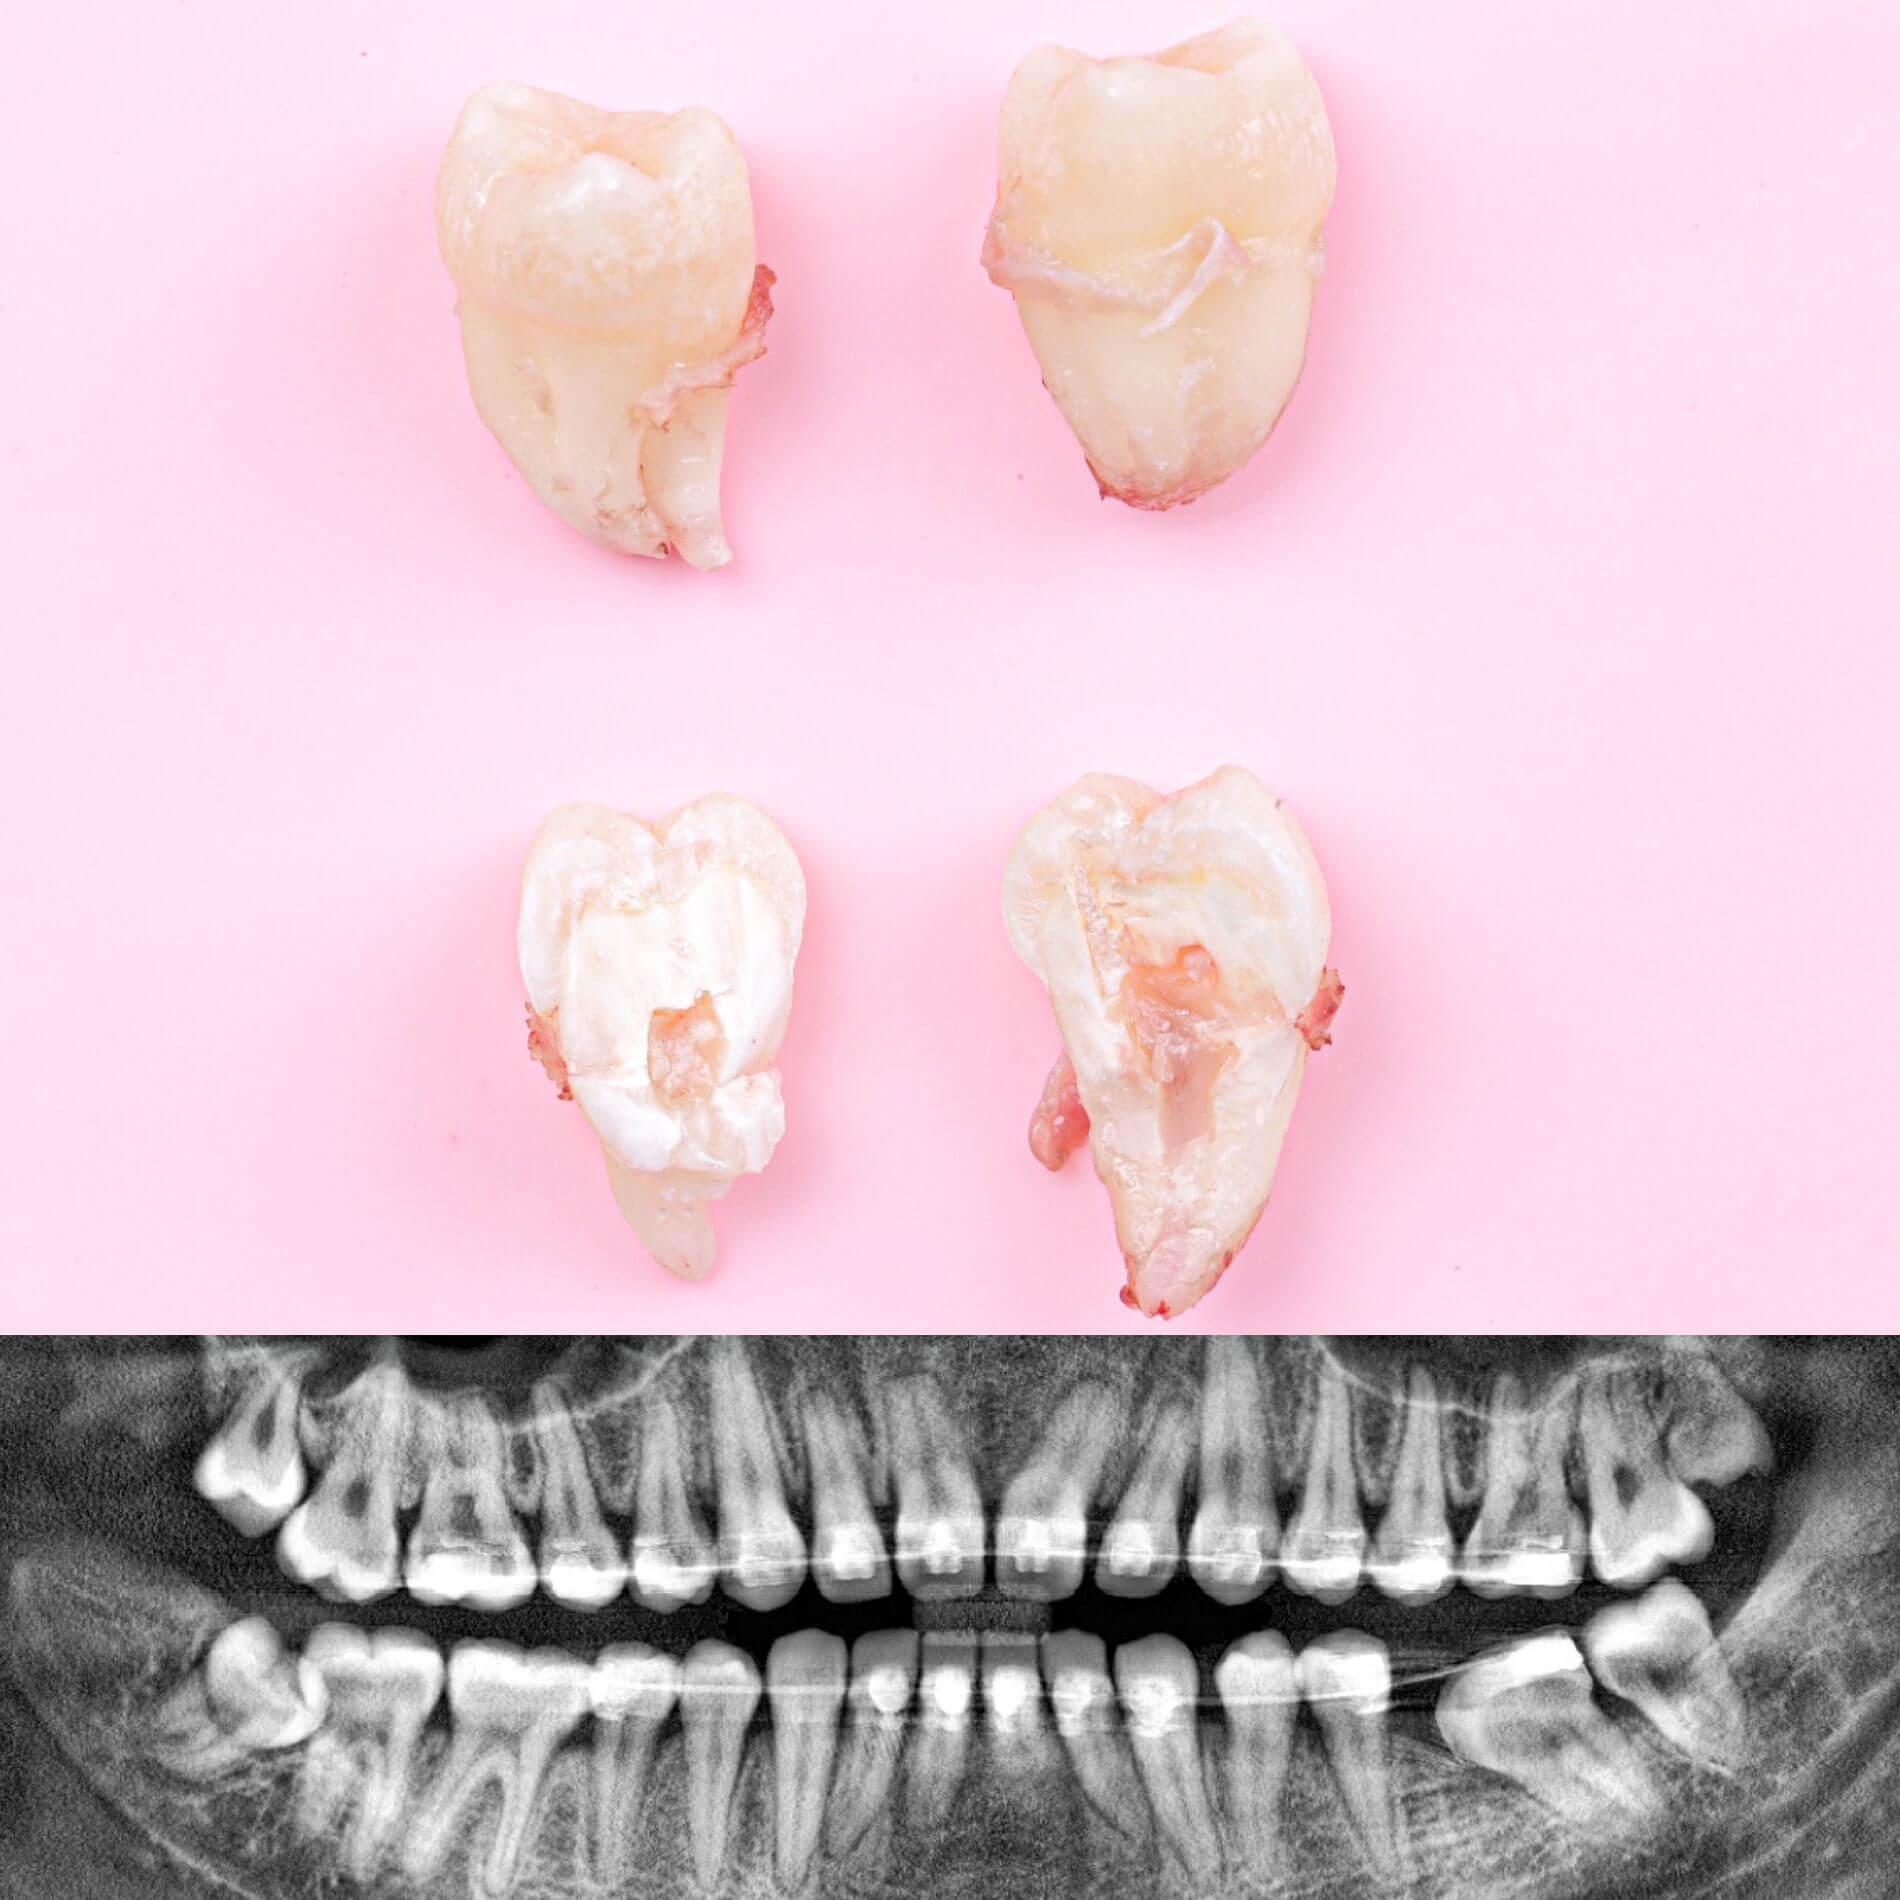

Галерея